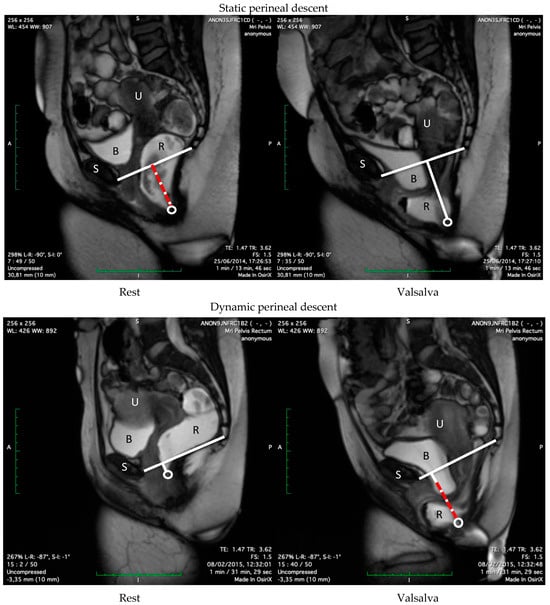

2.4. Imaging Analysis

Figure 1. Perineal descent on MRI: Static perineal descent (red dashed) i.e., large difference between position of the ARJ and the PCL at rest, with subsequent minimal difference in movement of the ARJ during maximum Valsalva. Dynamic perineal descent (red dashed) i.e., large difference in movement of the ARJ during maximum Valsalva, following a minimal difference between position of the ARJ and the PCL at rest. S = symphysis pubis, B = bladder, R = rectum, U = uterus, circle = ARJ.